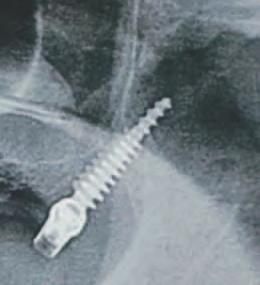

Implantur le pter go d ene au fost def n te ca f nd „[un] mplant plasat pr n tuberoz tatea max lară în placa pter go dă” (f g. 4). Implantur le pter go d ene traversează tuberoz tatea max lară d n reg un le molarulu secund sau terț edentat pentru a se ancora în osul cort cal dens format de peretele poster or al tuberoz tăț max lare, procesul or zontal al osulu palat n ș procesul pter go d al osulu sfeno d.

Aceste mplantur au, de ob ce , un d ametru între 3,5 mm ș 4,3 mm ș o lung me cupr nsă între 18 mm ș 25 mm, cu angulaț ale bontur lor mult -un t de până la 60 grade. Astfel de lung m sunt necesare pentru a as gura că vârful mplantulu se ancorează în osul cort cal al sutur pter gopalat ne după ce traversează țesutul gros adesea prezent în tuberoz tatea max lară. Angulaț a dep nde ș de ungh ul peretelu poster or al s nusulu max lar ș de prox m tatea acestu a față de peretele poster or al tuberoz tăț maxlare. Implantur le pter go d ene au adesea vârfur agres ve în formă de V, ascuț te ș auto-f letante pentru a as gura o ancorare stab lă la mplan-

tare ș colete cu f lete larg pentru a compr ma osul de dens tate scăzută d n reg unea tuberoz tăț max lare.